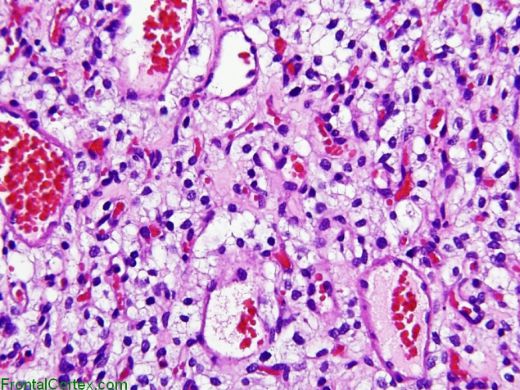

What CNS tumor is seen in the histology slide below? _____